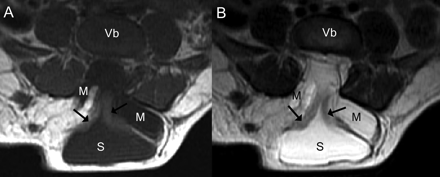

一个已经男孩看到一个突出的无痛性软质量(8×7厘米)在出生后骶区,与完整的皮肤覆盖。超声显示囊性扩张的远端中央管周围扩张蛛网膜下腔(图1)。MRI证实的诊断终端脊髓囊肿状突出的典型发现trumpetlike扩口syringocele和脑脊髓膜突出(图2)。

图2

核磁共振成像

轴向t1 (A)和t2加权磁共振扫描显示类似的描述(B)作为超声。箭头指向变形和流离失所的脊髓。M =脑脊髓膜突出;S = syringocele;Vb =椎体。